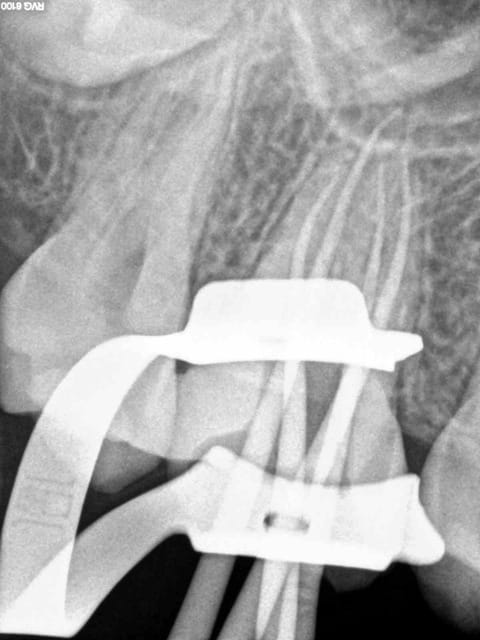

C'est quoi la proba d'avoir une deuxième bio à 5 canaux en 2 semaines?

(la radio excentrée est dégueulasse, mais ça montre les doubles courbures, quelques peu minimisées par l'angulateur...